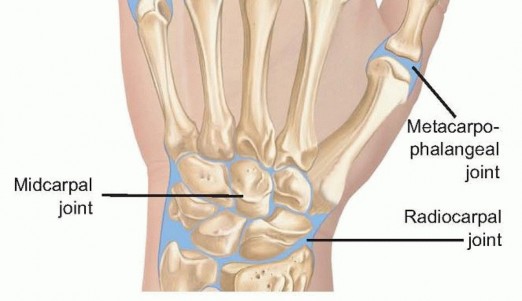

A masterful surgical approach to the infected hand and wrist requires an intimate, three-dimensional understanding of the regional anatomy. The interphalangeal (IP) and metacarpophalangeal (MCP) joints are complex articulations stabilized by a delicate interplay of capsuloligamentous and musculotendinous structures. The MCP joints are condyloid articulations permitting flexion, extension, abduction, and adduction. Their stability is primarily governed by the proper and accessory collateral ligaments and the robust volar plate. Crucially, the proper collateral ligaments are eccentric; they are lax in extension (allowing abduction/adduction) and maximally taut in 70 to 90 degrees of flexion. Conversely, the interphalangeal joints are true hinge joints. Understanding these tensioning patterns is vital during postoperative splinting to prevent debilitating contractures.

The wrist joint is an intricate biomechanical marvel comprising the radiocarpal, midcarpal, and distal radioulnar joints (DRUJ). The radiocarpal joint is entirely separated from the DRUJ by the triangular fibrocartilage complex (TFCC), provided the TFCC is intact. However, in the setting of chronic degenerative tears or acute trauma, these compartments may communicate, allowing purulence to spread from the radiocarpal space into the DRUJ. Dorsally, the wrist capsule is accessible between the extensor tendon compartments. Lister's tubercle serves as the paramount osseous landmark, separating the second dorsal compartment (extensor carpi radialis longus and brevis) from the third compartment (extensor pollicis longus). Surgical approaches, whether open or arthroscopic, heavily rely on these intervals to access the joint safely while avoiding the superficial sensory branches of the radial and ulnar nerves.